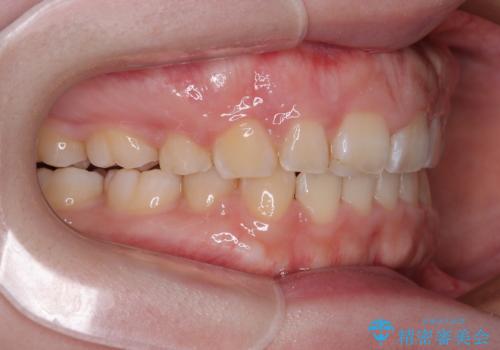

抜歯矯正を行ったことで、顎先のつっぱり感や口元の閉じにくさを解消することができました。